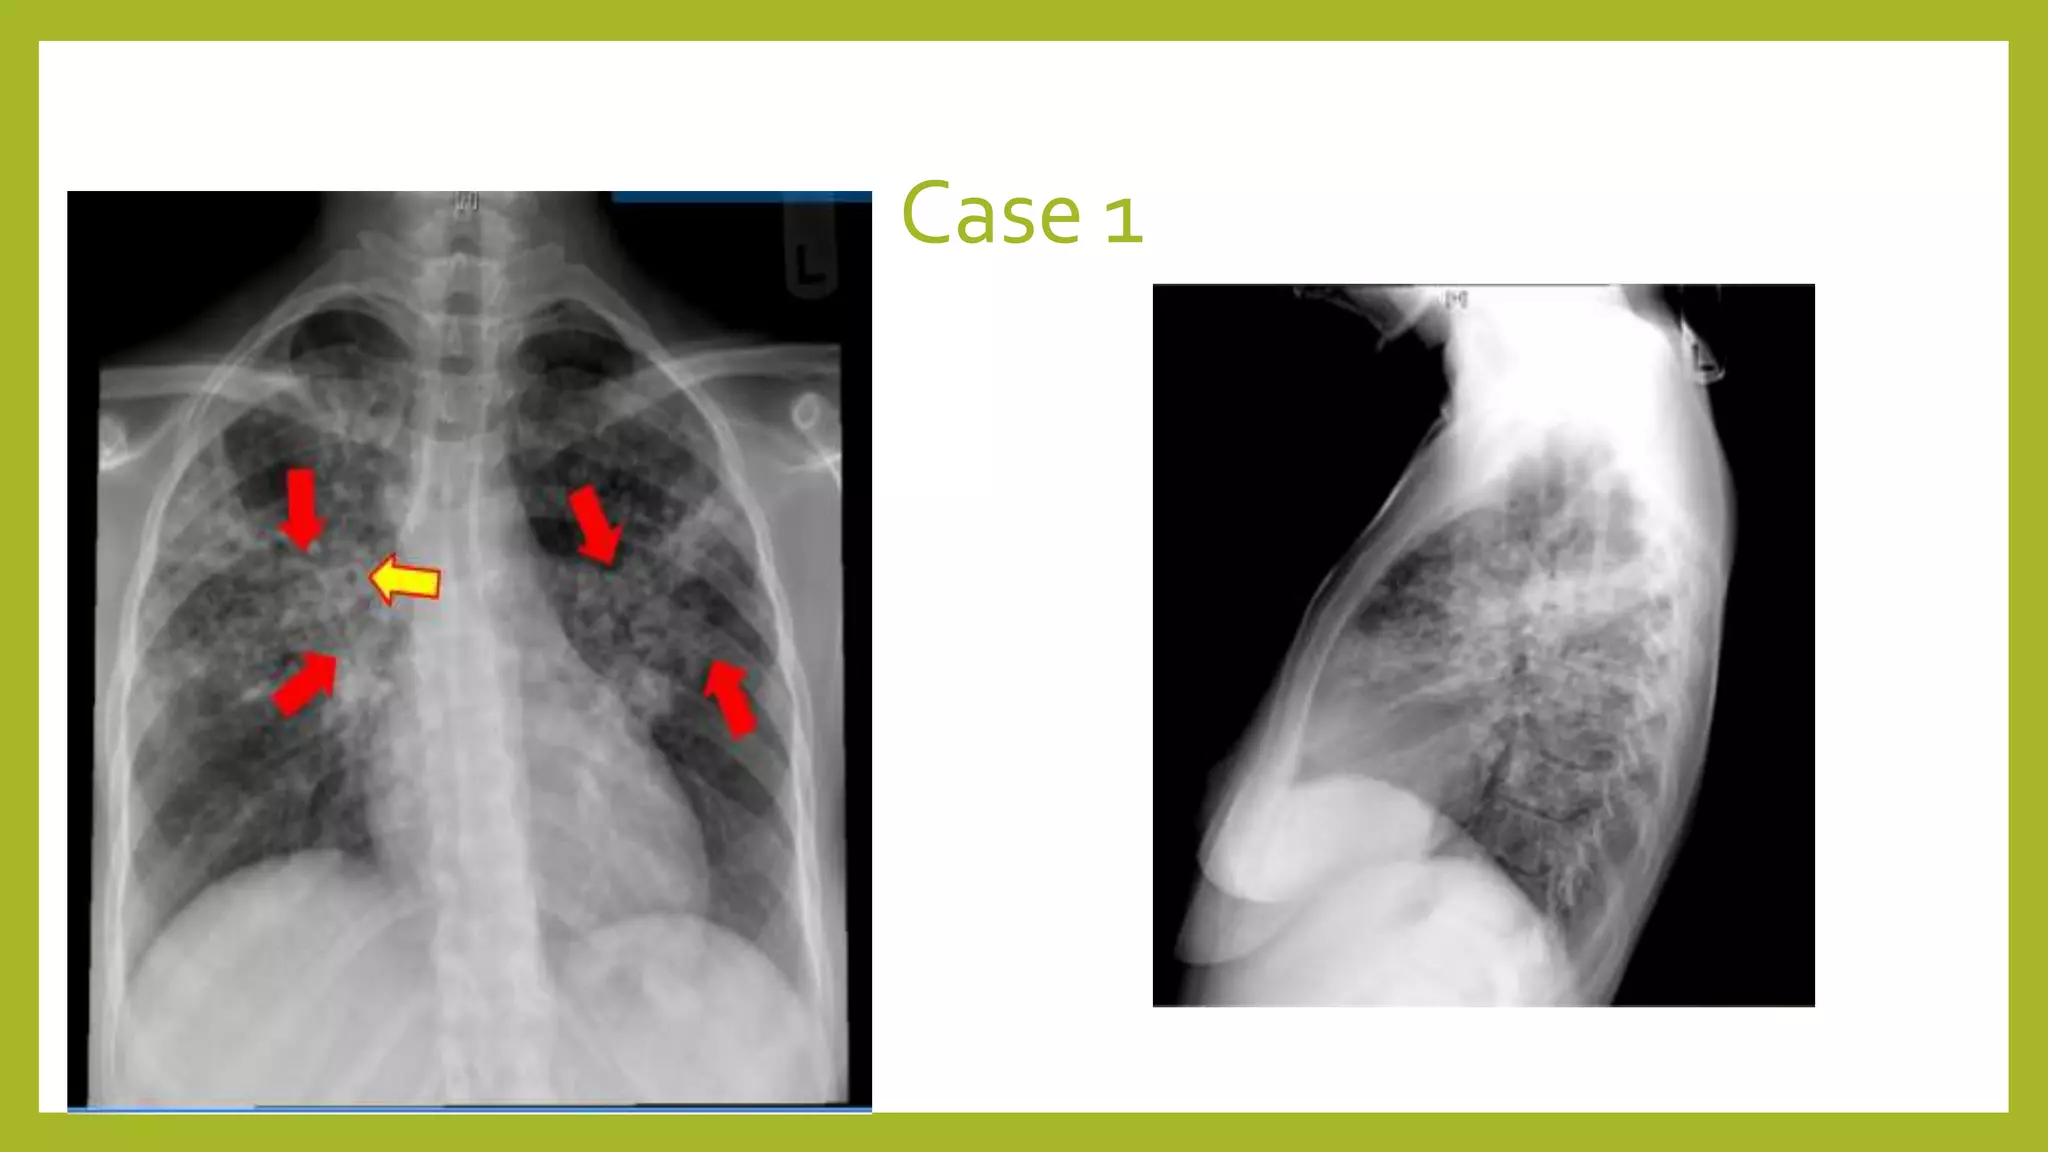

The document provides guidance on approaching and interpreting chest x-rays (CXR). It outlines steps to check the name, date and quality of the film, systematically scan the CXR looking for abnormalities, and determine if the lungs appear too white or black. Specific signs are described to help localize abnormalities, including the cardiac silhouette sign and pleural effusion signs. Examples are given of respiratory distress syndrome, tetralogy of fallot, transposition of great arteries, and total anomalous pulmonary venous return. The take home message is to summarize positive findings, compare to prior CXRs if available, and confirm findings with a radiologist.